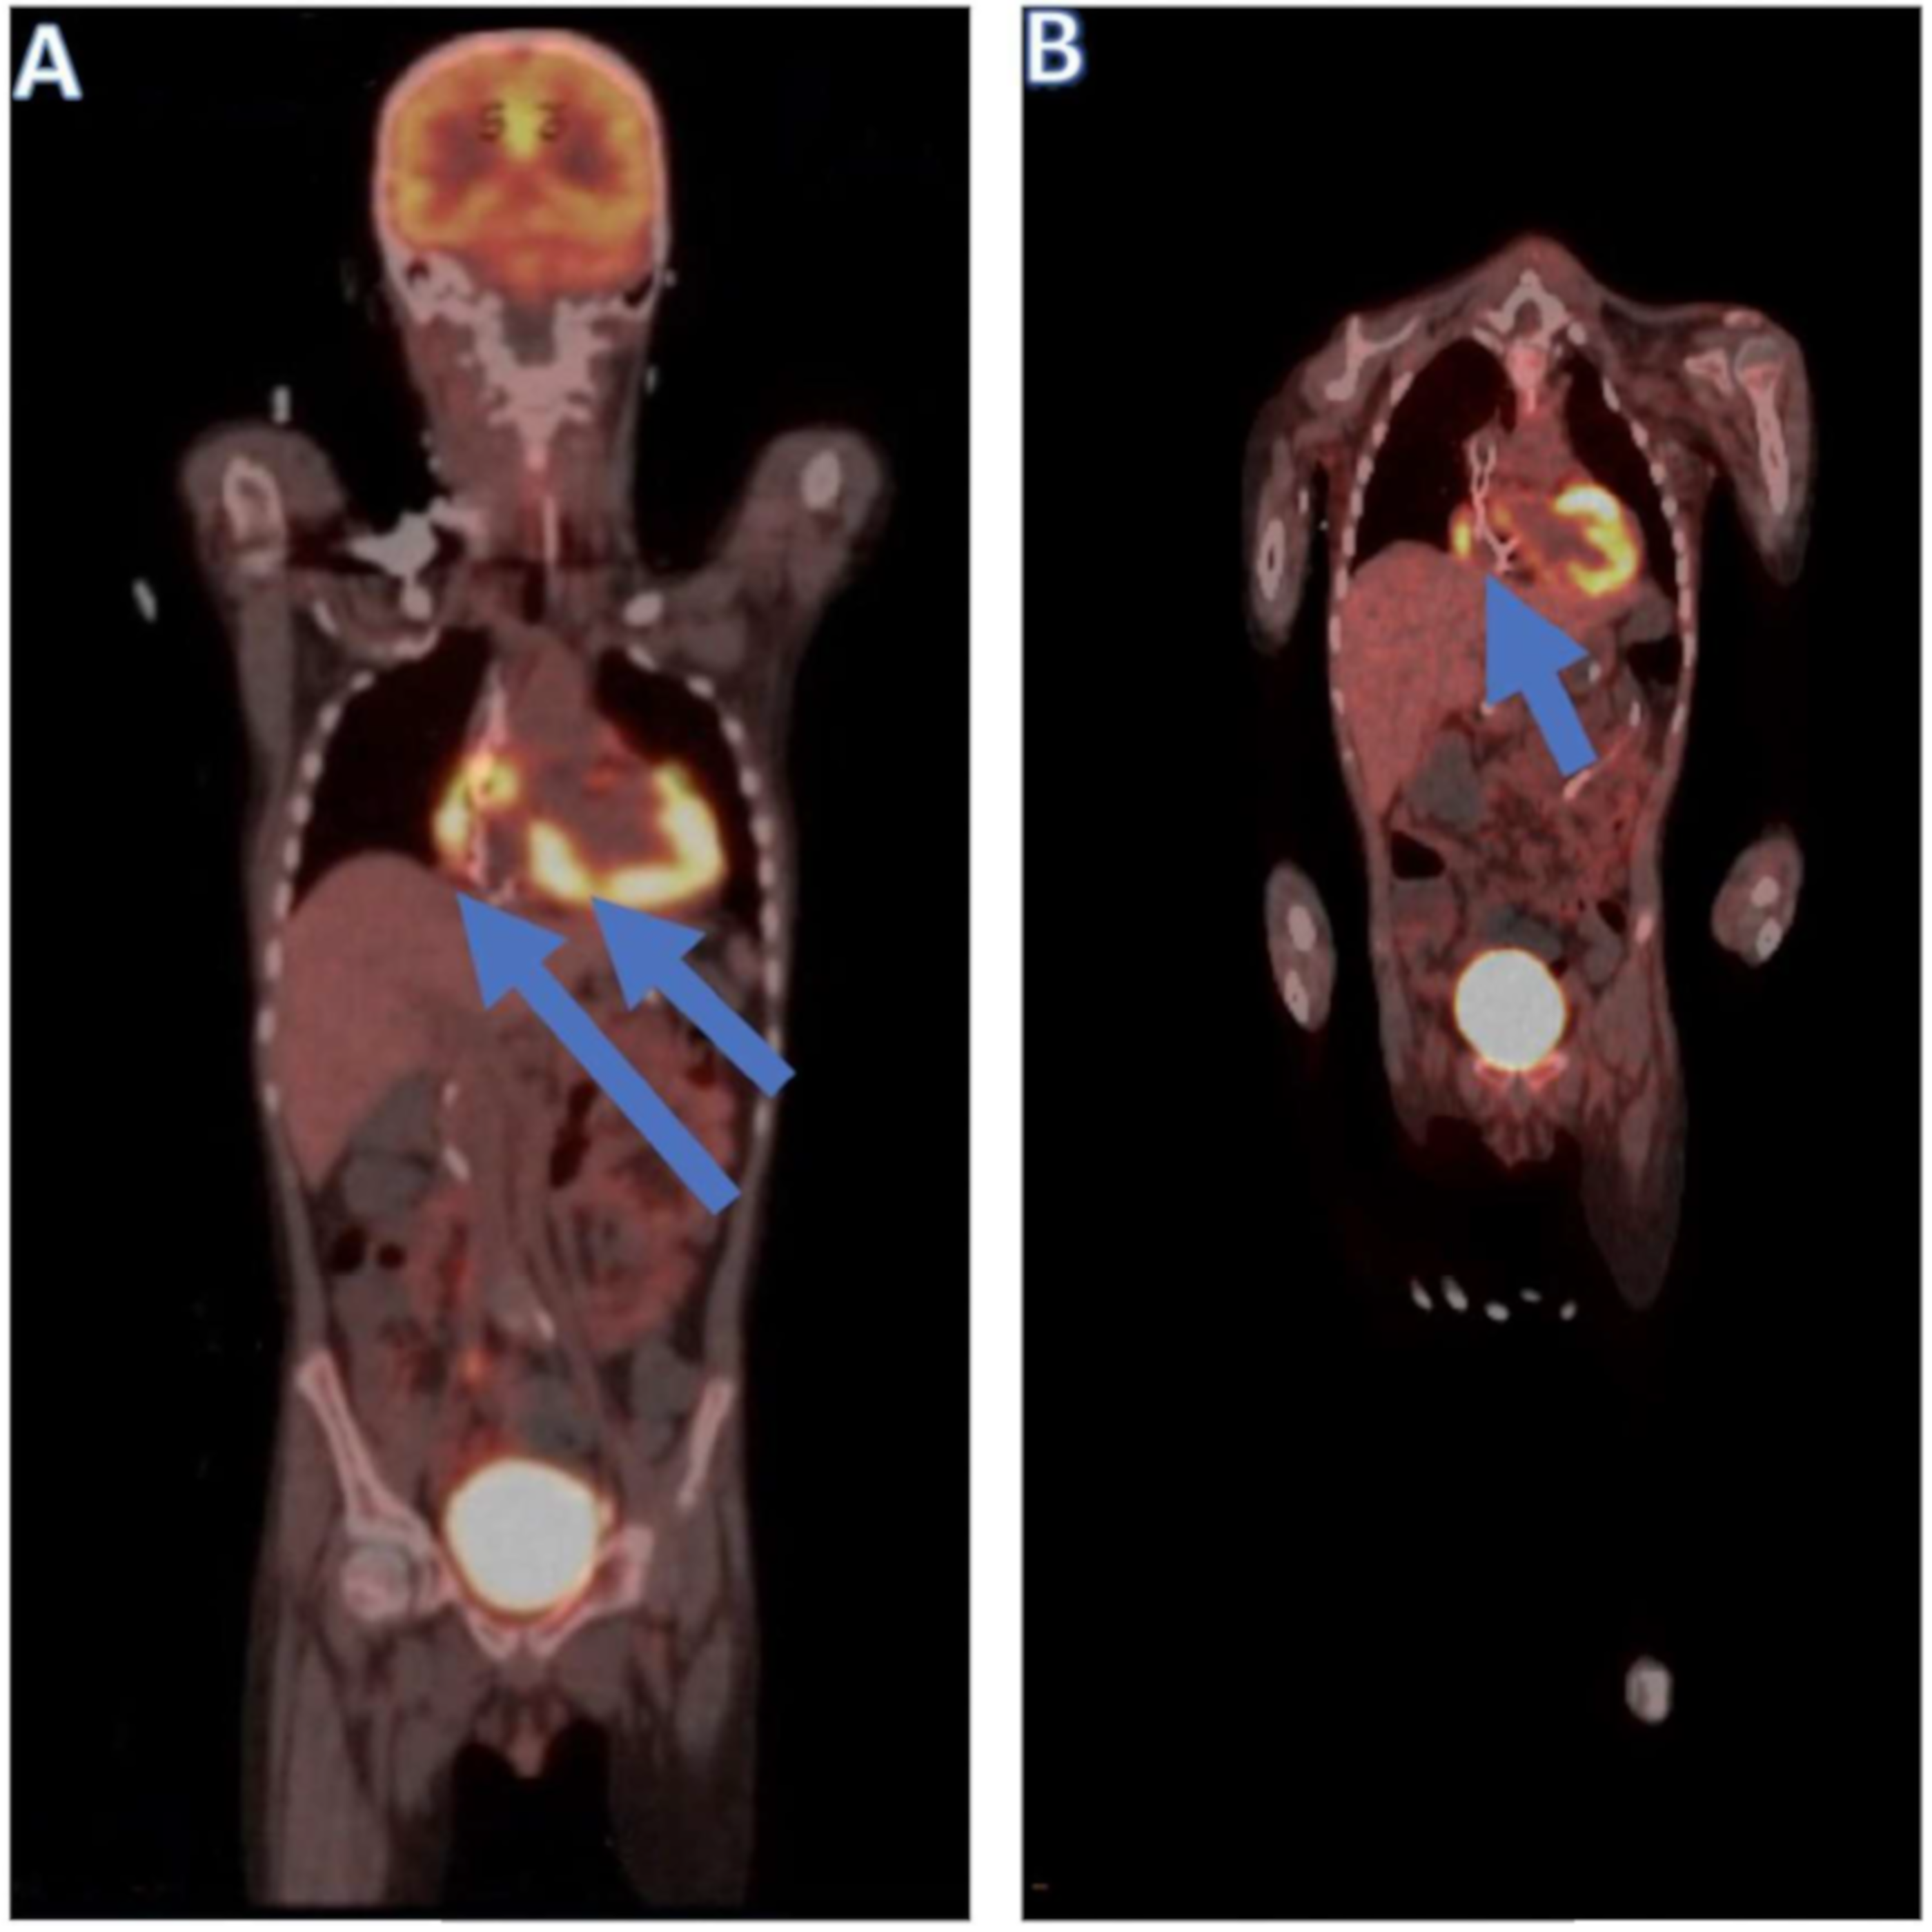

| 16 months | Post-transplantation relapse 1 | R-MOAD

| Symptomatic cardiac relapse |